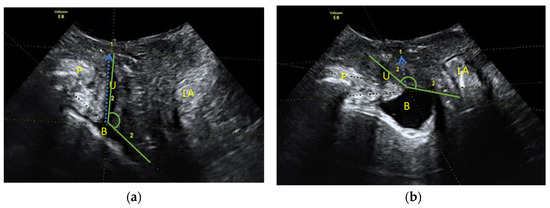

- Distance between the sling and the posterior urethral wall is considered adequate if between 3–5 mm (in 2D transperineal). With a high-frequency probe, it is possible to accurately calculate the distance between the sling and the urethral light.

- Sling shape (at rest and Valsalva). The tapes usually have a flat shape at rest, determined by their shape parallel to the urethral lumen, and they deform into a “C” shape in Valsalva in relation to the tension caused by the increase in intra-abdominal pressure.

- Concordance of the urethral movement with that of the sling during the Valsalva (urethral kinking).